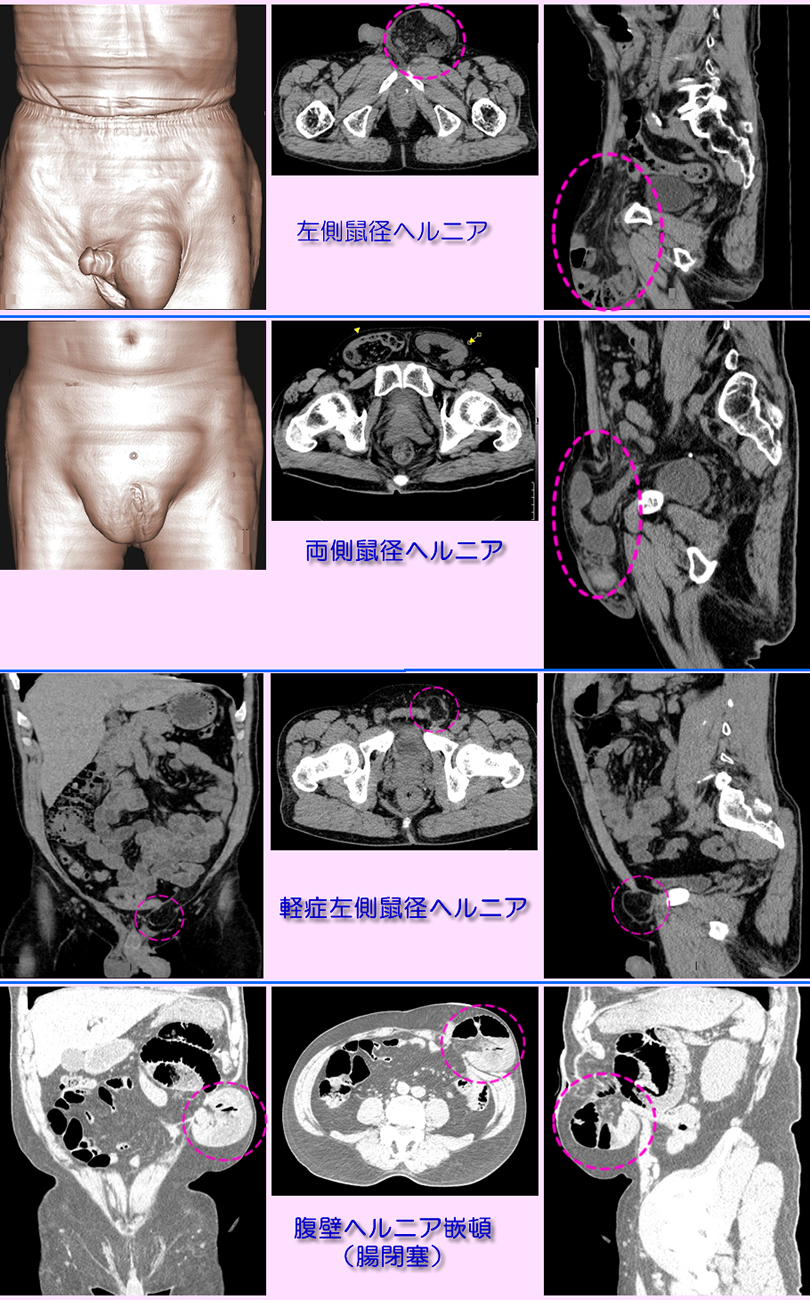

ヘルニア(鼠径・腹壁)

診断

ヘルニアの部位により鼠径部、陰嚢部、大腿部の膨隆、腹壁ヘルニアは 手術部位の腹壁が薄くなり、腸管が薄く膨隆した腹壁部位に入り込む。CTは膨隆部の内容物(腸管)の確認や範囲(重度)の評価に有用。下段にヘルニアのMDCT検査画像を提示します。